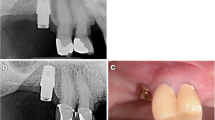

A representative case of a rehabilitated female patient is visualised in Fig. 4a–h and Fig. 5a–d (radiograms).

Contrary to conventional hollow-screw implants (only marginal gap), a problem of the expandable implant is the presence of gaps down to the apical region. Former microbial assessment of different implant-abutment interfaces displayed that none of the marginal connections had the capacity to prevent microbial leakage [63,64,65]. Therefore, an apical microleakage (comparable to distractable implants and endodontically treated teeth) might be a disadvantage of the evolved implant system [66, 67]. However, according to the manufacturer’s information, a microbiological study revealed no microbial leakage through the expanded implants. Over the follow-up period, we equally did not observe any inflammatory signs in the apical region, neither clinically nor radiologically (Figs. 4b and 5c–d). Nevertheless, this aspect should be analysed under mechanical loading in vitro. Based on an earlier animal histologic study [47], as well as a clinical up-to-40-month study [46], which referred to comparable apically expandable implants, authors did not report any periapical inflammatory complications. To eliminate the potential risk of deep intrabony microleakage, it is questionable whether equal biomechanical stability values can be achieved only by the macrothread design avoiding any deep microgaps.